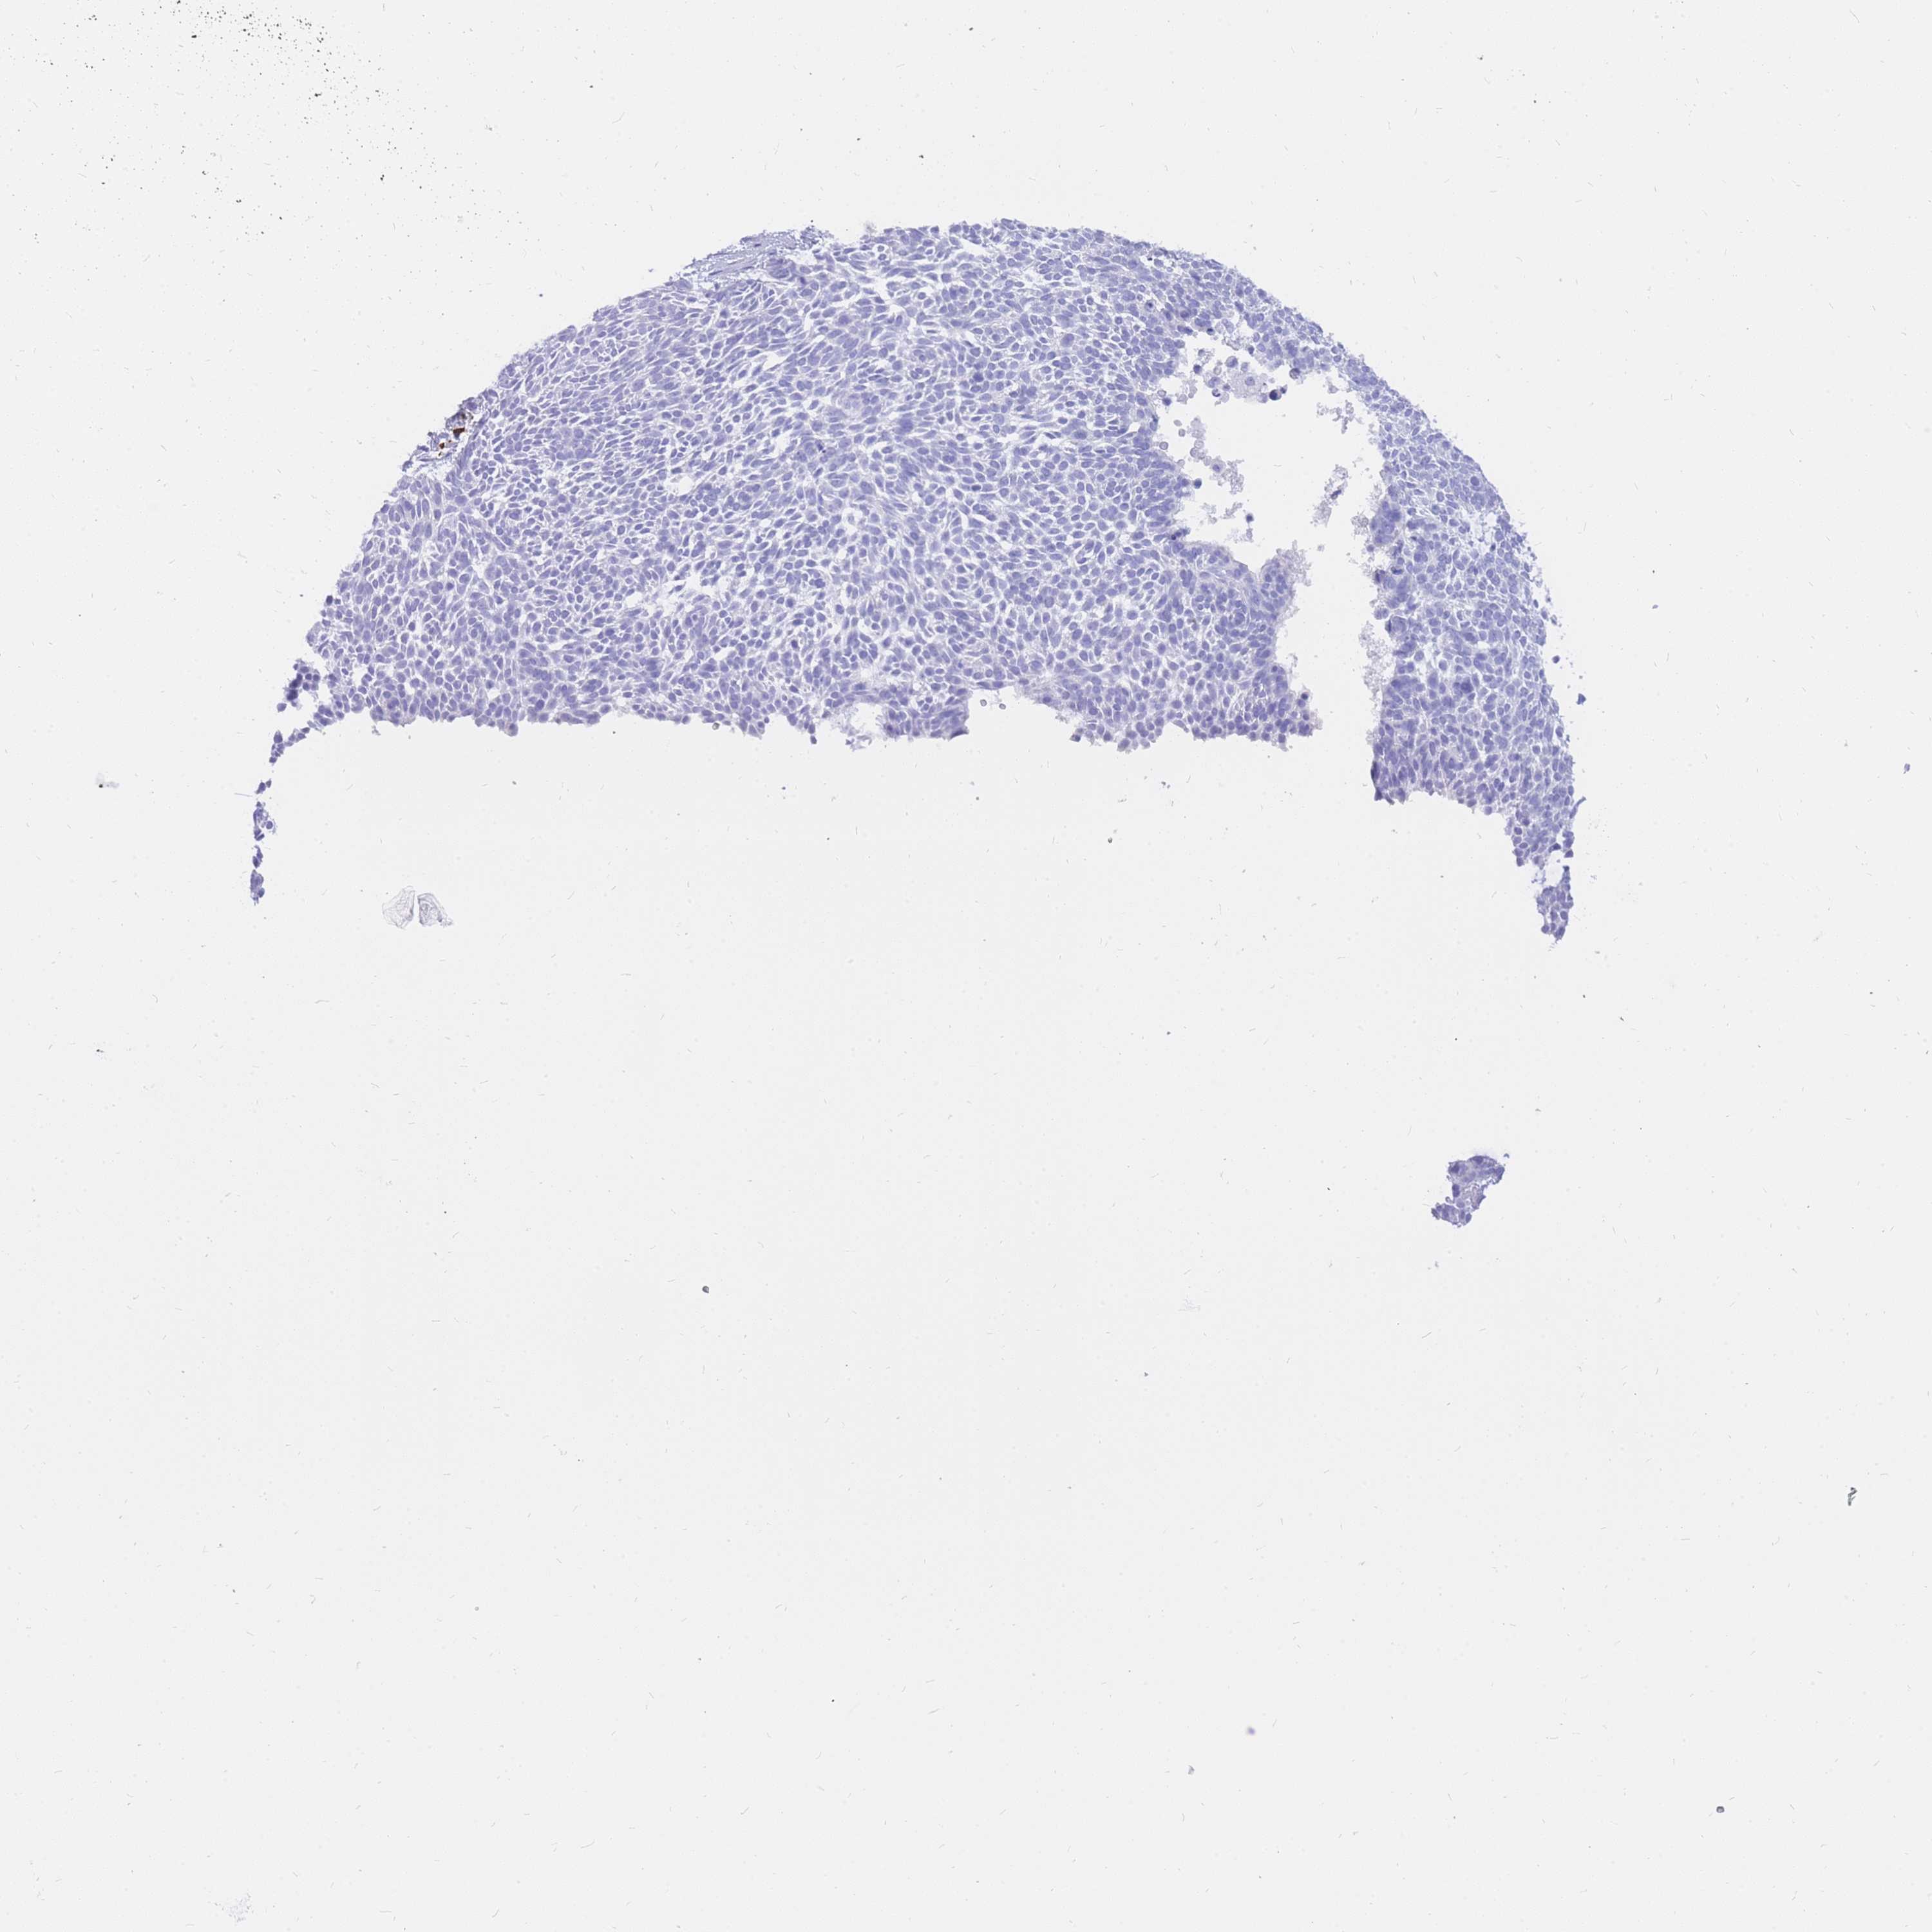

SKIN CANCER - Protein expressioni

A mouse-over function shows sample information and annotation data. Click on an image to view it in a full screen mode. Samples can be filtered based on level of antibody staining by selecting one or several of the following categories: high, medium, low and not detected. The assay and annotation is described here.

Antibody stainingi

Antibody staining in the annotated cell types in the current human tissue is reported as not detected, low, medium, or high, based on conventional immunohistochemistry profiling in selected tissues. This score is based on the combination of the staining intensity and fraction of stained cells.

Each image is clickable and will lead to virtual microscopy that enables deeper exploration of all samples and also displays staining intensity scores, fraction scores and subcellular localization as well as patient and tissue information for each sample.

Antibody HPA049749

Staining

High

Medium

Low

Not detected

Intensity

Strong

Moderate

Weak

Negative

Quantity

>75%

75%-25%

<25%

None

Location

Nuclear

Cytoplasmic/membranous

Cytoplasmic/membranous,nuclear

Basal cell carcinoma